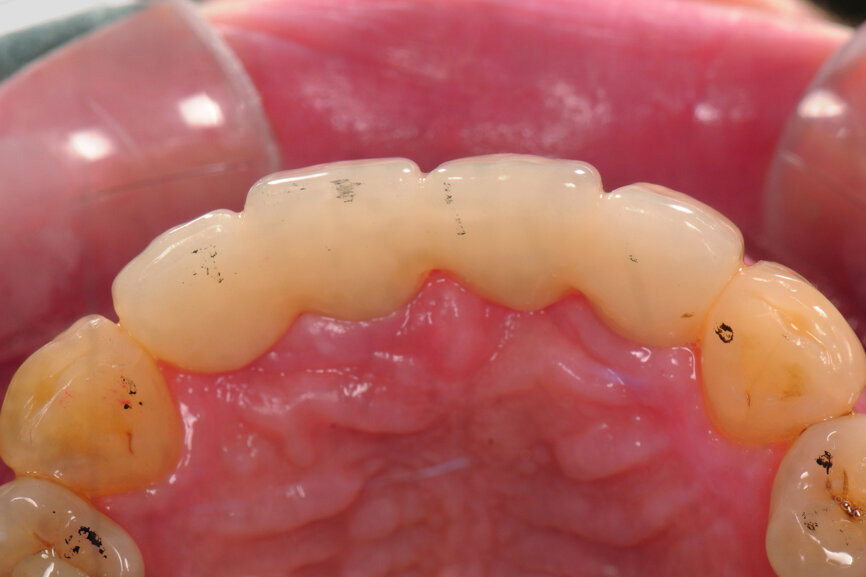

Fig. 14: Provisional restoration on the model.

Teeth #12, 21 and 22 were extracted. Tooth #11 underwent early implantation and tooth #22 immediate implantation with GBR (Figs. 5 & 6). After three months of healing, osseointegration had taken place. An implant level impression was taken for fabricating a provisional bridge supported by temporary abutments for teeth #12–22. The technician modified the shape of the artificial gingiva on the model in order to form the proper gingival curve and emergence profile, then finished the provisional bridge, while the dentist modified the gingival shape using an olive-shaped bur intraorally (Figs. 7–18).

After three months of healing, both hard and soft tissue around the implants had been well maintained, providing a sufficient foundation for the maxillary restoration. In order to form a good gingival shape, either the provisional restoration can be adjusted step by step or the shape of the soft tissue can be designed first, the provisional restoration manufactured to meet the aesthetic demand directly, then the soft tissue intraorally adjusted and reshaped.

In this case, we followed the second option. After using an olive-shaped bur to adjust the form of the gingiva under the pontic, making it match the provisional restoration, which had already been well designed and manufactured, a perfect soft-tissue outcome was achieved.